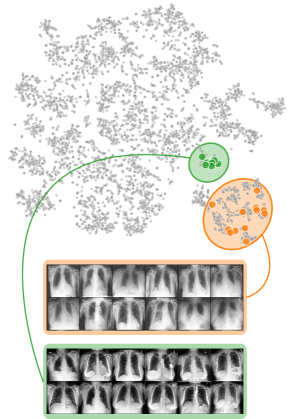

4.2 Model Perspective – Detecting Spurious Representations

In contrast to detecting spurious samples, recent work focuses on identifying spurious model internals directly. This aligns with mechanistic interpretability, which seeks to decipher the internal mechanics of DNNs [56, 31, 13]. As outlined in Sec. 3.1, various global XAIs methods aim to explain the role of individual neurons, and these insights can be leveraged to detect spurious model internals by clustering learned concepts and identifying outliers. Given input data with samples, Pahde et al. [59] compute spatially aggregated relevances . Subsequently, they compute the pairwise cosine distance per column (i.e., channel/concept) and embed the resulting distance matrix in a low-dimensional space using dimension reduction techniques like t-Distributed Stochastic Neighbor Embedding (t-SNE) [71] or Uniform Manifold Approximation and Projection (UMAP) [49]. This low-dimensional embedding can be visualized to identify outliers through human inspection or anomaly detection algorithms, such as the Local Outlier Factor [12]. In summary, outlier representations can be identified in an embedding representation , obtained as

| (3) |

where reduces the dimension to , and the pairwise distance function is applied along all channel dimensions in the latent representation , either given by activations or relevance scores for layer . Note that this approach assumes over-parameterization resulting in redundant neurons, allowing to distinguish between similar and dissimilar concept representations. An example is shown in Fig. 4 (bottom), where latent relevance scores from a ResNet50 model trained for melanoma detection are used to identify outlier concepts, specifically a cluster focusing on band-aids rather than clinically relevant features. Notably, Eq. 3 can easily be extended to find outlier directions instead of neurons. Specifically, this involves a linear transformation of latent representations using the directions of interest, e.g., obtained in unsupervised manner as described in Sec. 3.1.

Similarly, DORA embeds a pairwise distance matrix of neuron representations into 2D, but proposes a data-agnostic approach and a tailored distance function [16]. Specifically, they generate ActMax samples as concept representation for neurons, referred to as natural Activation-Maximization signals (n-AMS). Each neuron is represented by a representation activation vector , measuring how much other neurons activate on the given n-AMS, and compute pairwise distances between the vectors. The resulting distance matrix is embedded into lower dimension to identify outlier representations. Notably, instead of generating ActMax samples, this approach can also be applied on real samples from a reference dataset.